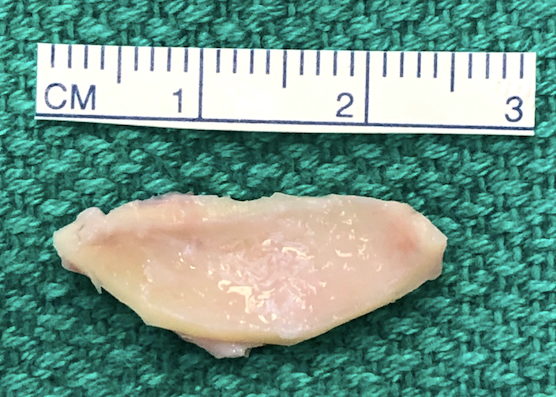

Next, the butterfly graft is harvested with enough length to span as far laterally on each side as necessary to correct the collapsed nasal valves. See below for description of graft harvesting. The graft is then trimmed at the edges and contoured. The superior edge of the graft is beveled to further reduce the risk of supratip fullness and allow for a smooth nasal dorsal counter (Figure 4). The graft is then placed in the dorsal pocket. If adequate dorsal reduction was achieved, the nasal dorsum should be smooth. Additional re-excision to deepen the dorsal pocket may be required.

Though harvesting of the cartilage comes from within the conchal bowl, the incision is placed laterally on the peak of the antihelix (Figure 6). This prevents post-operative webbing and cicatricial scaring. Additionally, the scar hides nicely on the natural peak of the antihelix. The conchal bowl and corresponding posterior auricle are injected with a 50:50 mixture of 1% lidocaine with 1:100,000 and 0.25% bupivacaine with 1:200,000 epinephrine. The incision is made with a 15 blade to the cartilage. A freer or tenotomy scissor is used to establish the subperiosteal plane. The conchal skin is elevated off the cartilage dissecting medially. Soft tissue elevation is the performed on the posterior surface of the cartilage. The graft, measuring approximately 10 mm x 25-30 mm, is sharply excised from the conchal cartilage with a 15 blade and placed in a saline bath. Hemostasis is obtained in the wound bed, and the incision is closed with a 5-0 fast absorbing gut suture in a running fashion. A bolster is placed to eliminate dead space and prevent a post-operative hematoma. A 5” x 9” occlusive petroleum gauze is rolled and placed snuggly in the conchal bowl. A 3-0 Nylon suture is placed transmurally through the conchal bowl with a non-adherent gauze on the posterior auricle to protect the skin. Bacitracin ointment is applied to the incision and bolster.